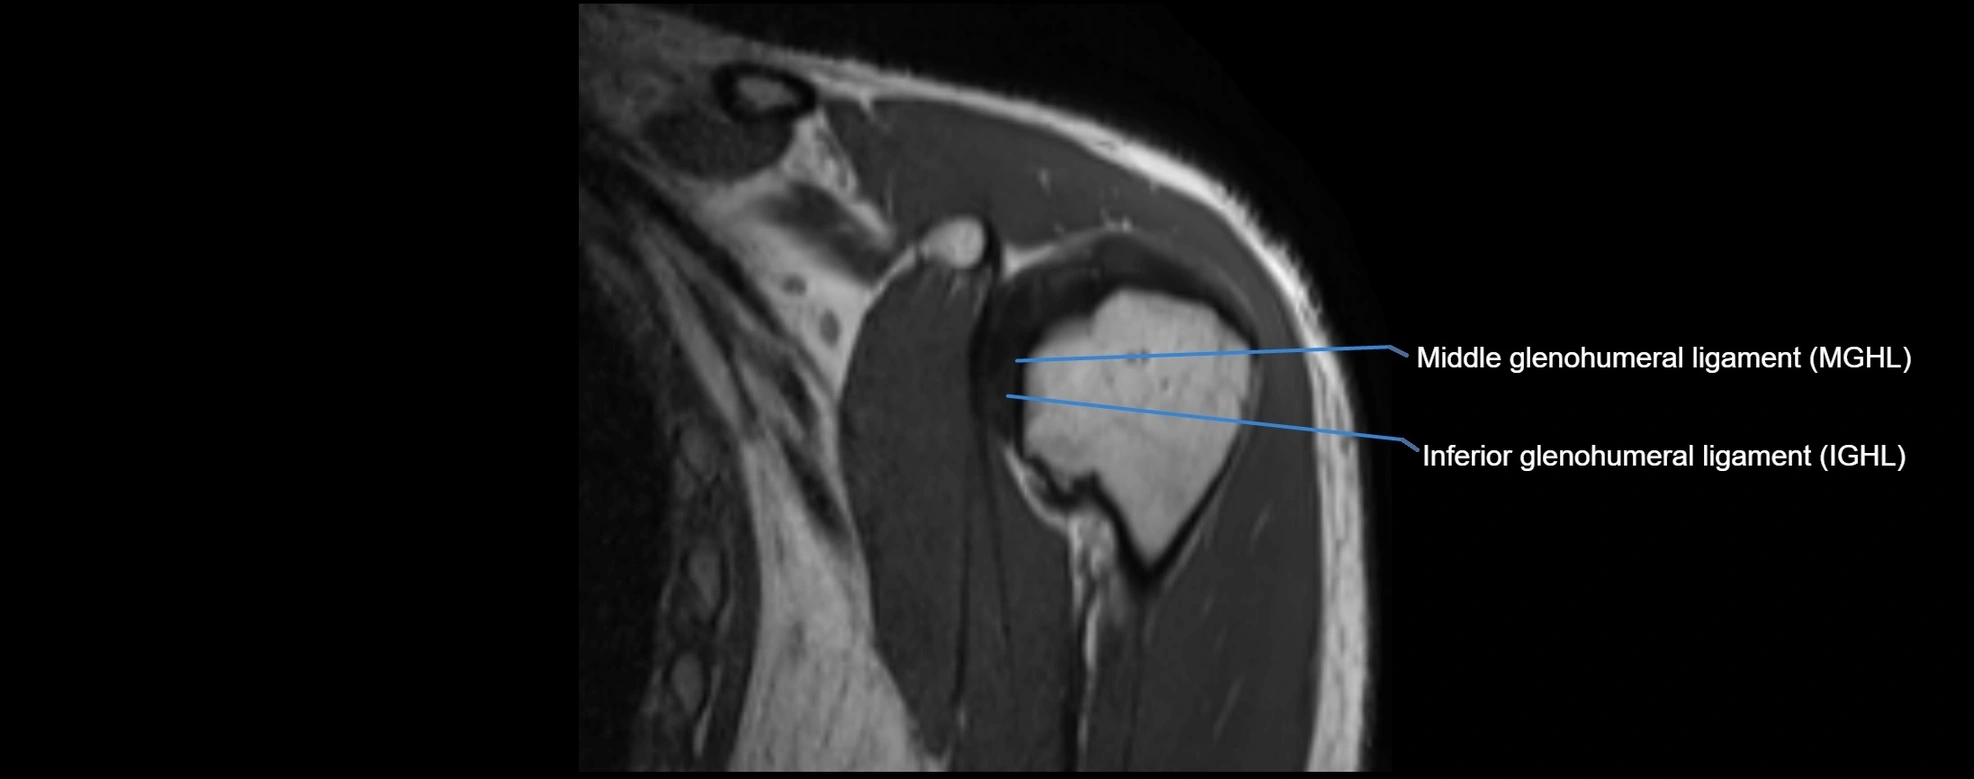

MRI images

image